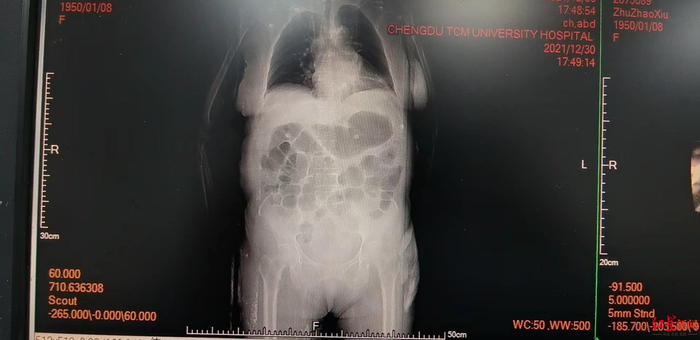

近日,成都中医药大学附属医院肾内二科就收治了一名生吞3个鱼胆“清热”的72岁女性患者,导致急性肝功能衰竭、肾功能衰竭等多器官衰竭,让老人命悬一线。最终经过20天的治疗,这名72岁的患者脱离了生命危险。

“患者到医院的时候,已经没有尿了。”赵良斌表示,当时,患者不仅腹痛腹胀等症状没有好转,还有了咳嗽时遗尿,重度黄疸导致全身皮肤发黄,皮肤瘙痒严重等症状。从检验数据上来看,朱婆婆的总胆红素高达139.7,而正常值在21以内,丙氨酸氨基转移酶的正常值是40,朱婆婆的检查数据大于1100,“直接爆表,仪器都测不出来了。”赵良斌说,门冬氨酸转移酶、肌酐、尿酸等多个检查数据都严重超标,还有重度低钙血症,随时都有生命危险。